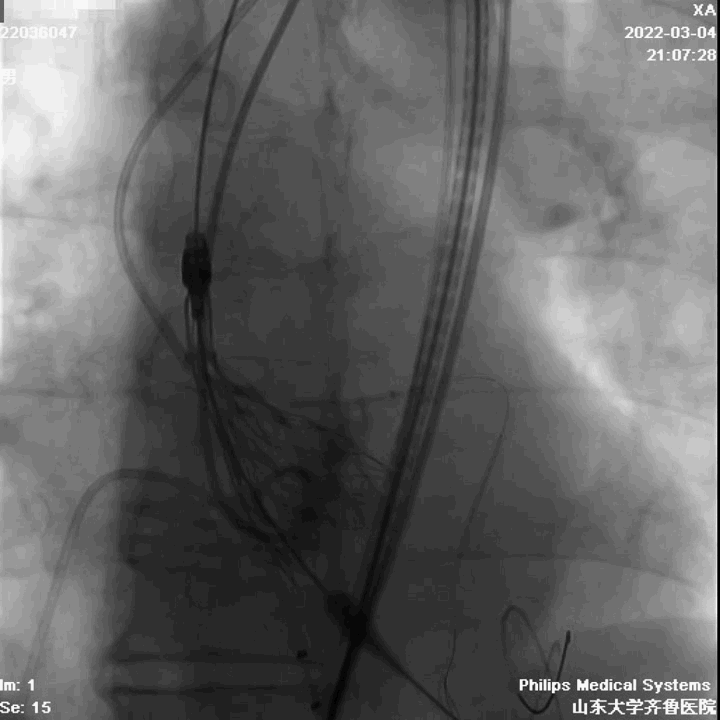

手术过程

第二例病人同样为高难度病例,Type1型L-R融合二叶瓣,钙化积分1300,瓣叶增厚、轻度钙化,钙化分布于瓣叶及左右瓣叶融合脊。

瓣环周长87.4mm,平均径27.1mm。LVOT周长90.5mm,平均径28.5mm。

瓣上4mm/6mm,预估可推开空间周长81.8mm/75.8mm。

在陈院长指导下,李传保主任团队顺利迅速完成了手术,目前病人恢复良好,均已出院。